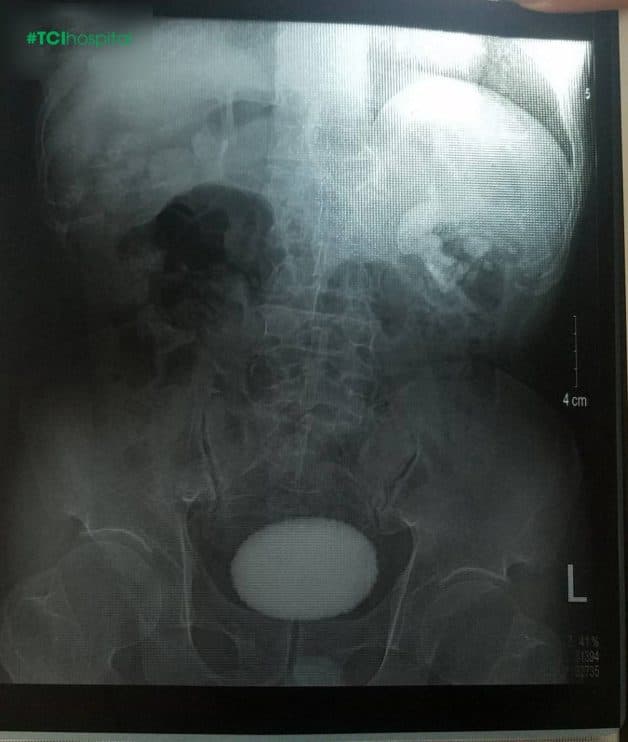

Sỏi tiết niệu là khối chất rắn một hoặc nhiều viên kích thước, hình dạng khác nhau nằm tại bất kỳ vị trí nào trên đường tiết niệu. Sỏi có thể nằm tại thận, niệu quản, bàng quang, niệu đạo hoặc có thể là ở lớn hơn 1 vị trí của cơ quan trên đường tiết niệu. Do đó sỏi tiết niệu bao gồm 4 loại sỏi đó là sỏi thận, sỏi niệu quản, sỏi bàng quang, sỏi niệu đạo.

Sỏi đường tiết niệu bao gồm các loại sỏi thận, sỏi bàng quang, sỏi niệu quản, sỏi niệu đạo với hình dạng và kích thước khác nhau

Mổ mở là phương pháp cuối cùng bác sĩ sẽ sử dụng cho người bệnh khi sỏi có kích thước lớn, sỏi san hô, bệnh nhân không đáp ứng được những phương pháp điều trị ít xâm lấn. Phương pháp điều trị này hiện nay ít được sử dụng hơn. Tuy nhiên khi sỏi có kích thước quá lớn, sỏi đã gây ra những biến chứng nếu không phát hiện và điều trị kịp thời, người bệnh bắt buộc phải sử dụng để đưa sỏi ra khỏi cơ thể.

Bệnh nhân mắc sỏi bàng quang kích thước lớn thực hiện mổ mở tại Thu Cúc TCI